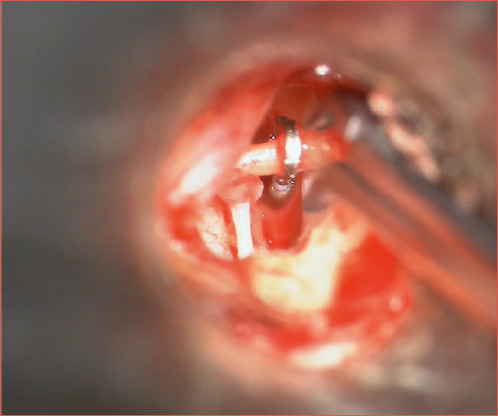

Update on stapes surgery.

Luca Bruschini, Francesco Lazzerini, Andrea De Vito, Francesca Forli, Stefano Berrettini